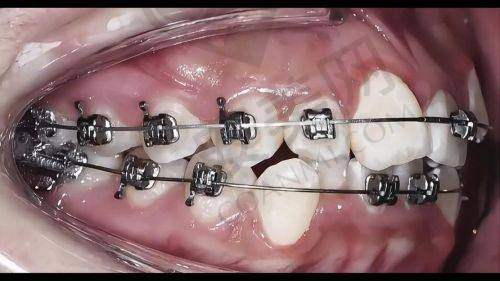

其次,他掌握了多种精良的矫正技术。如金属直丝自锁矫正,这种矫正器自带锁扣,可有效减少调整次数,缩短矫正周期,让患者更快拥有理想的牙齿。数字化隐形正畸则具有美观、舒适、可自行摘戴等优点,适合对美观要求较高的患者。

例如,有一位患者牙齿拥挤不齐,还有轻微的龅牙问题。韩永刚医生为他制定了金属直丝自锁矫正方案。在矫正过程中,医生根据患者的牙齿移动情况,适时调整矫正力度,更终患者的牙齿变得整齐美观,咬合功能也得到了改善。